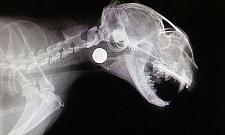

Młody i Kalinka to koty, które całe życie spędziły pod ziemią w kanałach. Nie znały zewnętrznych zagrożeń. Ich światem była ciemność, upał w kanale, a jedynym źródłem światła otwarty właz. - Patrzyła mu w oczy kiedy strzelał? Kalinka nie podchodzi blisko, ale nie boi się ludzi. Ma takie piękne, ufne oczy. Strzelił z góry, musiał dobrze wymierzyć, z bliska. Kula trafiła w oko i zatrzymała się w krtani. Strzelił do bezbronnego ufnego stworzenia... Chciałoby się krzyczeć i dorwać tę bestię - tak szokującego posta napisano na fanpage'u fundacji "Koty Spod Mostu" kilka tygodni temu, opatrując go zdjęciami postrzelonej w oko kotki. Kalinka jest jednym z kotów wolno żyjących w okolicach mostu Grota - Tam się urodziła i żyła od kilku lat, codziennie przez nas dokarmiana. Czekała na nas każdego dnia, czuła się bezpieczna. Aż wyczekała drania, który strzelił jej w oko. To cud, że żyje... Przeszła już operację usunięcia oka - informuje fundacja.

Kalinka przeszła w klinice operację. Z głowy wyciągnięto jej ołowianą kulę wielkości "prawie kociego oka". Po zdarzeniu teren kontrolowali policjanci i strażnicy miejscy, niestety sprawcy nie udało się złapać. - Uważam, że pocisk należy oddać do badania balistycznego. Na broń trzeba mieć pozwolenie, więc po śladach na kuli da się znaleźć strzelca. Nie wiadomo, czy następnym razem nie strzeli np. do dziecka - mówi pani Jadwiga, która mieszka w okolicy.